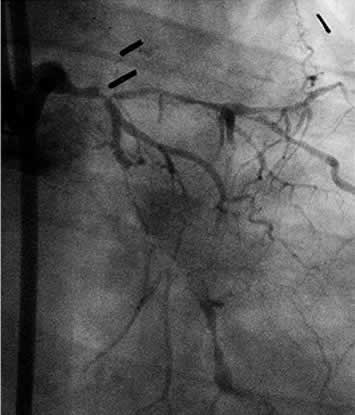

| Diagnosis:OMI (I), AP Present Illness: '90.1.18 CABG (LITA to LAD, SVG to RCA&LCX) '97.11.25 Stenting for #1-2 (Be STENT) '01.9.21 POBA for #1-2 (ISR) |

| Final CAG Findings:'01.8.25 LVG: asynergy (I), EF: 56% CAG: #5 90%, #6 99%, #11 90%, #13 100%, SVG to RCA & LCx 100% |

Wire not cross |